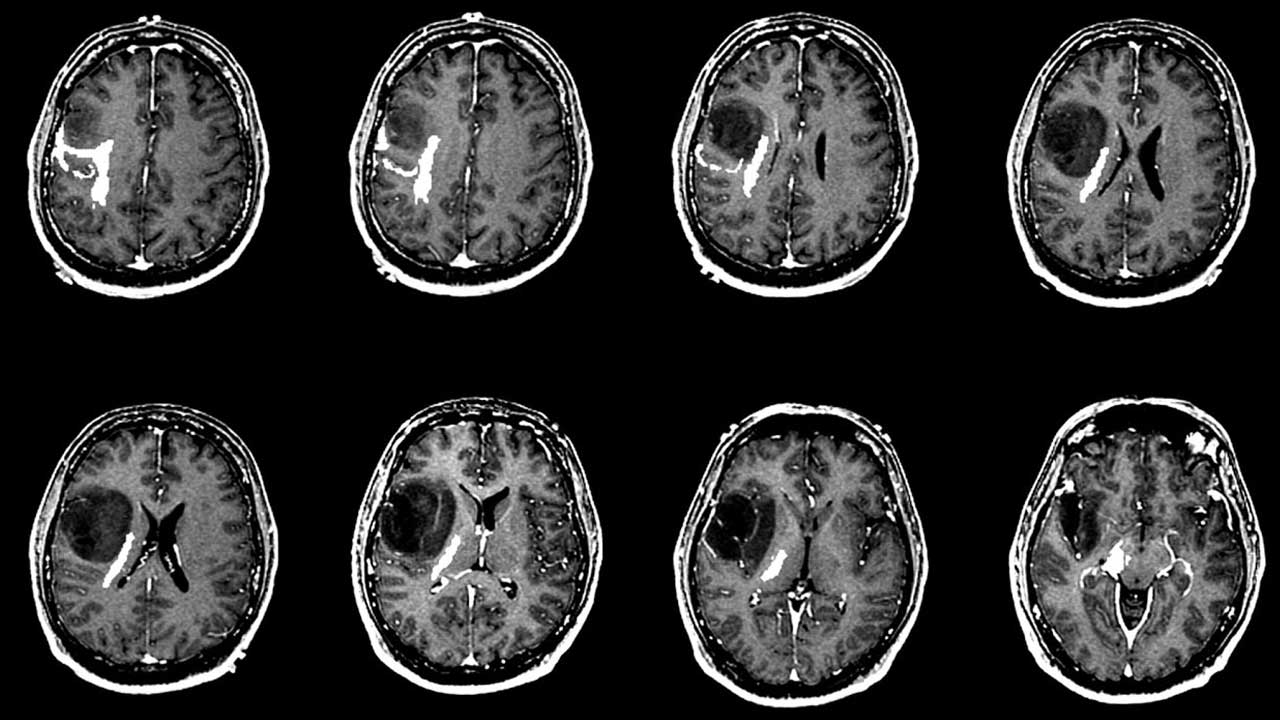

- Hazırlık: Ameliyat öncesinde hasta detaylı şekilde incelenir. MR ve fonksiyonel görüntüleme yöntemleriyle tümörün konumu belirlenir.